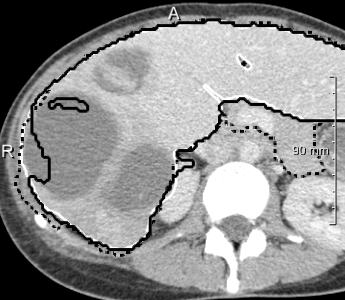

Example segmentations of the 2D U-net ensemble (2 mm) are illustrated in 3. Contour precision is limited by the resampling, but the model nicely excludes the vena cava and large hilar vessels much like in our training set. This hinders comparison against the state-of-art, since the reference masks from the SLIVER07 challenge (dashed in 3, right) partially include these vessels.

In most cases, the purely slice-wise application of the 2D U-net (dashed contours in 4) does not show any comb artifacts in orthogonal views. However, the ensemble classifier (solid contours) performs significantly better when the appearance is severely abnormal and 3D context is needed. In some cases, it locally performs worse, but has an overall better volumetric overlap (Wilcoxon signed-rank test, ). The ensemble models performed significantly better than the purely 2D transversal model on the same voxel size.